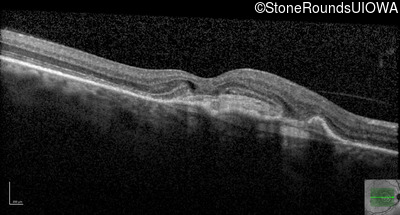

Age at visit: 59 years (Visit 3)

OD OS